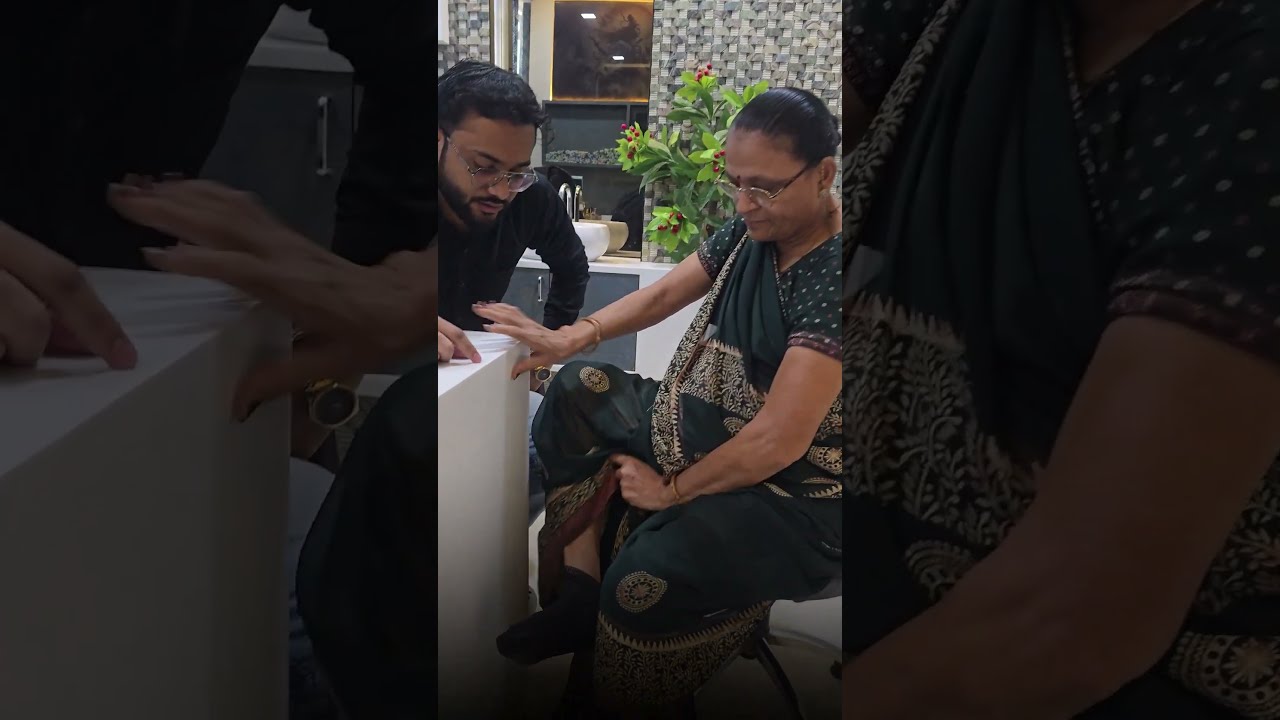

Rudra Orthopedic Hospital is one of the leading Orthopaedic Hospitals in Surat, providing advanced bone, joint, spine, and trauma care under the expert guidance of Dr. Keval S. Italiya, Consultant Orthopaedic Surgeon.

Our hospital is committed to providing ethical, precise, and result-oriented treatment for every patient.

Our mission is to provide result-oriented orthopedic care that focuses on long-term recovery, improved mobility, and better quality of life. We are committed to delivering treatments that are scientifically accurate, ethically guided, and centered around patient well-being.

Dr. Italiya has extensive expertise in trauma care, joint replacement surgeries (knee & hip), fracture management, arthritis treatment, and spine-related conditions. His approach focuses on long-term recovery and functional restoration rather than temporary pain relief.

Personalized physiotherapy programs for post-surgery recovery, sports injuries, arthritis, and chronic pain management.